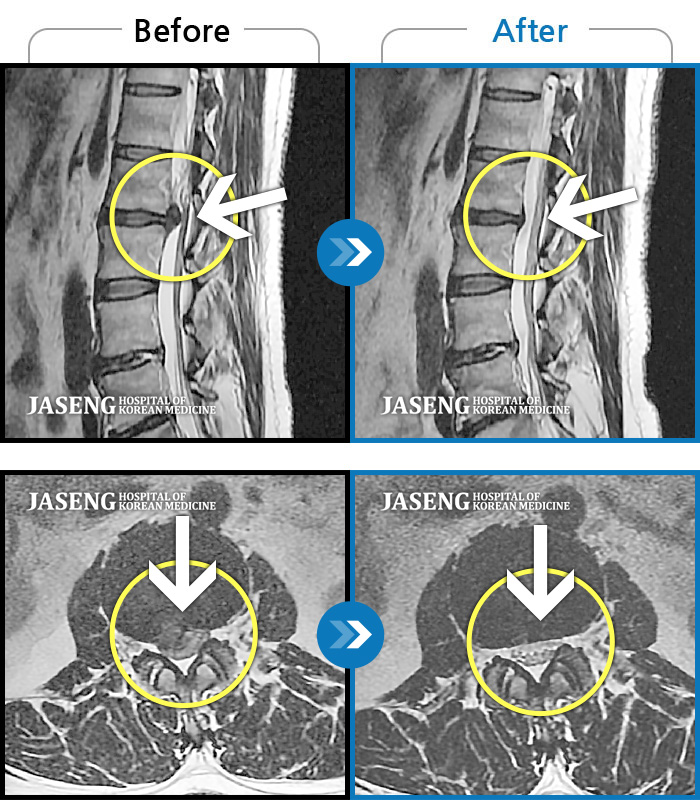

[뱸] 19.11.28~25.05.06